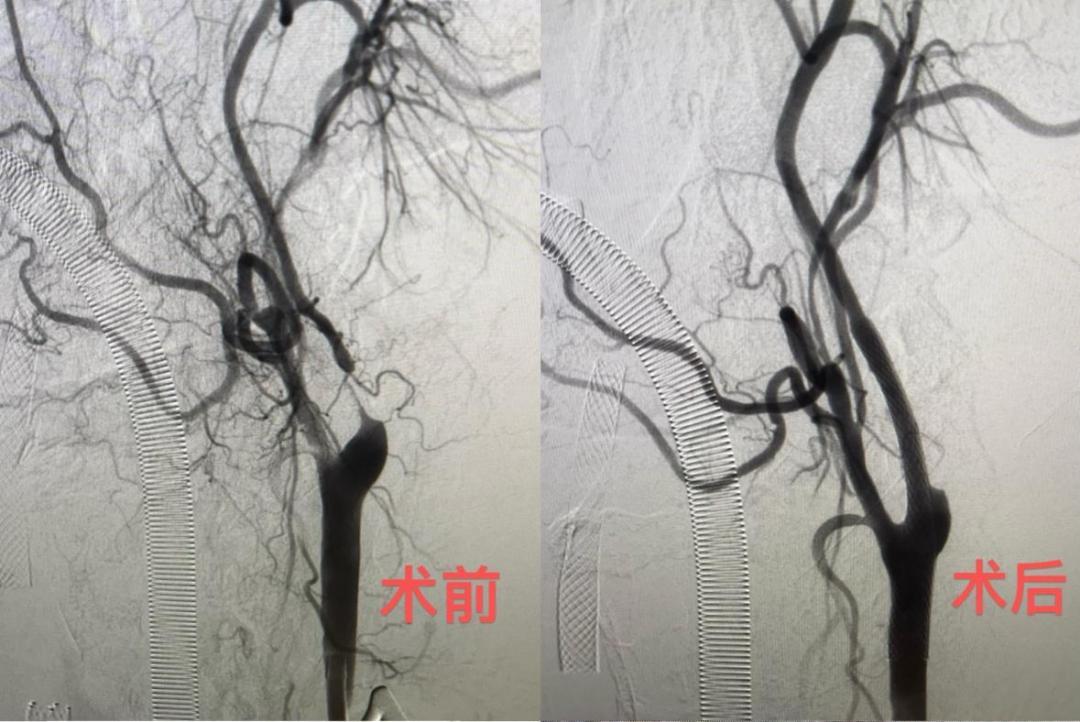

张先生今年68岁,因为头痛、耳鸣问题在外院多次看病,却没有找到病因解决问题,后来进行血管造影CT检查才发现左侧颈动脉严重狭窄,1.2厘米血管已经狭窄达90%,几乎断流。

陈光忠团队为其实施了华南首例颈动脉狭窄治疗新技术——经颈动脉血运重建术(TCAR)。手术直接在颈动脉上穿刺,阻断血流约20分钟,再进行球囊扩张与支架植入。“最关键的操作是进行了血流逆向保护”,陈光忠说,就像开个外挂一样,在体外接驳一条人工血管,从颈动脉接到股静脉,里面有一个特别密的保护网,能兜住绝大部分脱落的斑块栓子,“这样我们在放球囊扩张血管时,就不用太担心血栓脱落流到脑血管里。”该术式海外临床数据显示,术后30天患者卒中事件的发生率为1.4%,比颈动脉支架成形术(CAS)减少了约3.6%。手术不经过主动脉弓,避开了颅神经损伤,降低了脑梗、心梗的发生风险,让颈动脉狭窄的治疗更安全、更有效。